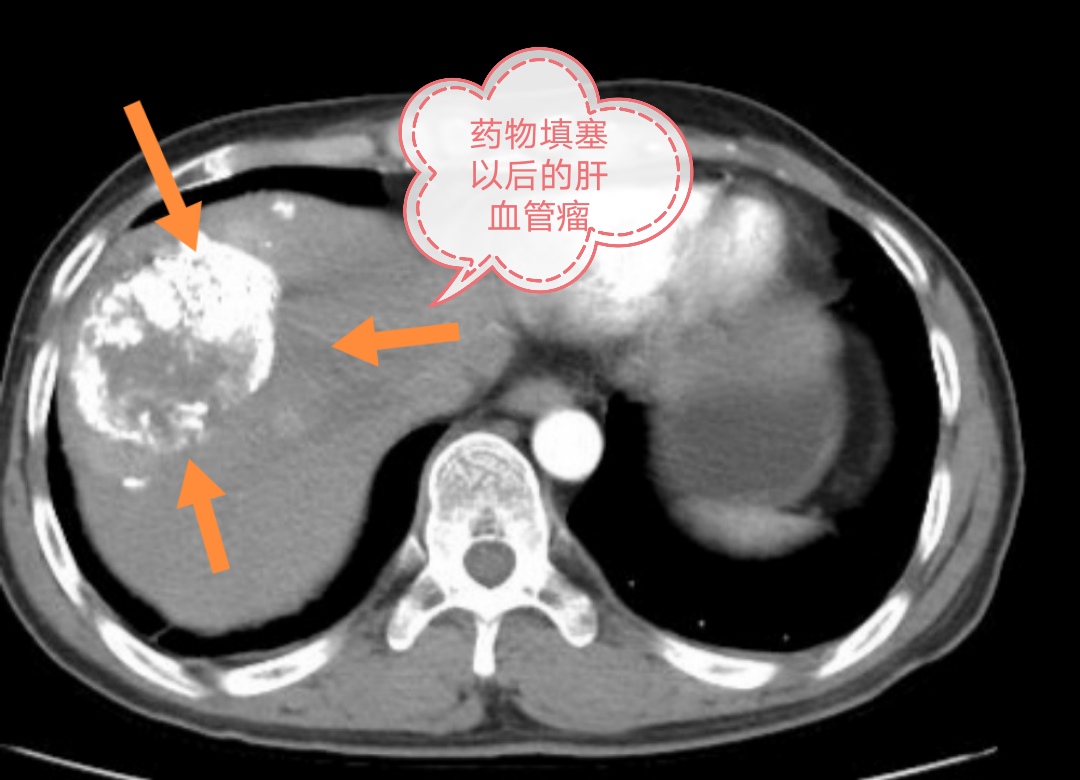

退出细管子后,大管子造影,能看到血管瘤的血管完全不显影了,被药物充填了。然而正常的肝脏血管不受影响,所以她本人几乎感觉不到有啥不舒服。

术后第三天复查肝、肾功能、血常规、电解质等化验指标无异常,她本人也没有啥不舒服的感觉,就复查CT后出院回家。